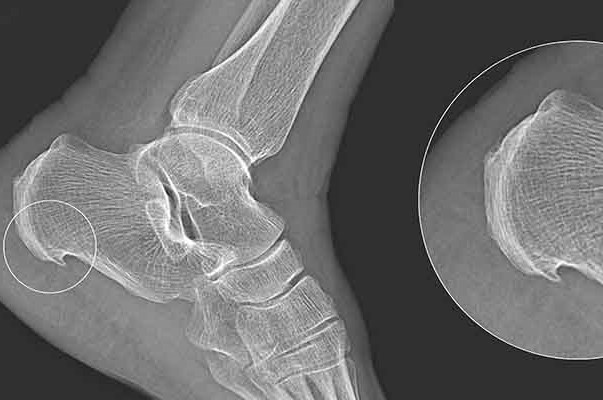

Pain in the foot and ankle joint is a fairly common problem that occurs in patients, especially those who are physically active. Ankle pain can be related to pain in the bone itself, pain in the tissues around the bone, such as the tendons of the fibular muscles, or it can be pain related to ligament damage, such as after an ankle sprain.